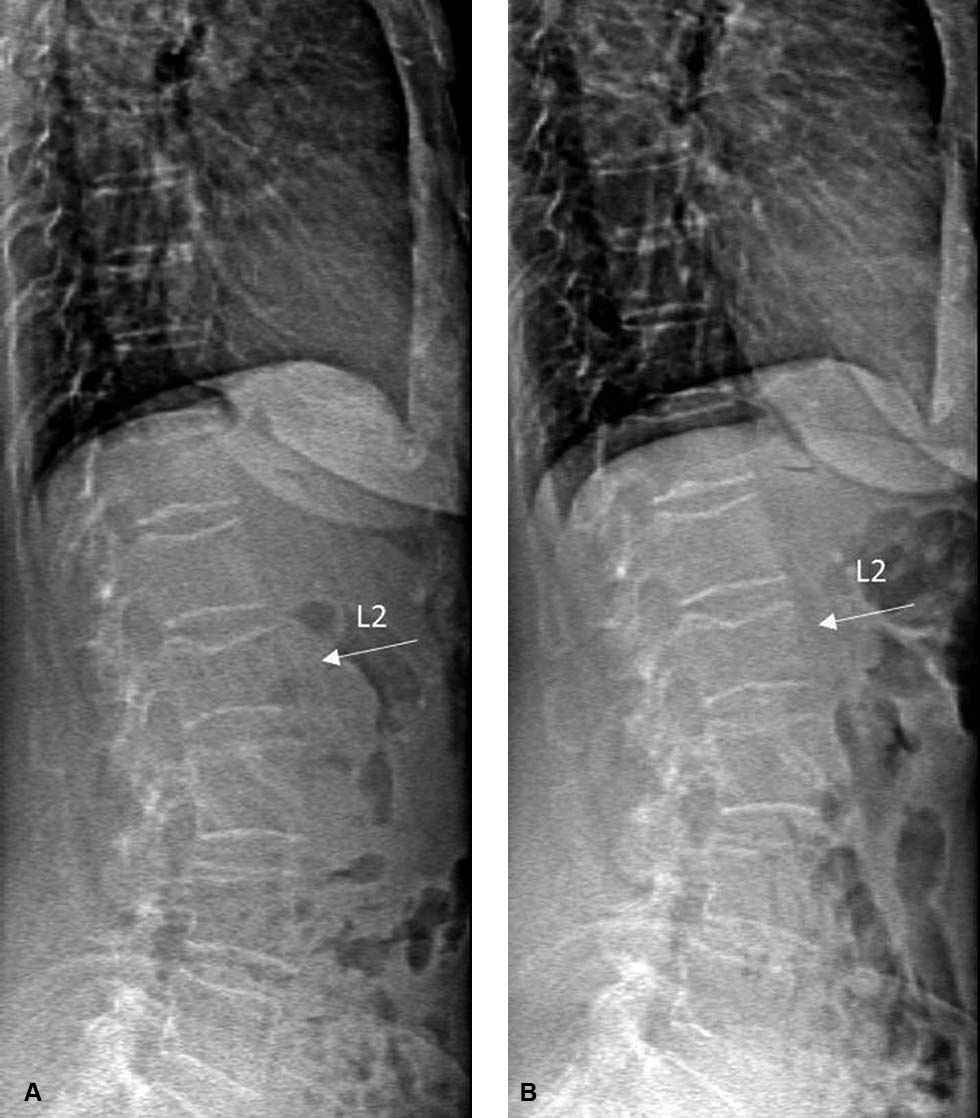

De NHG-Standaard Fractuurpreventie adviseert osteoporosemedicatie niet langer dan vijf jaar te gebruiken vanwege de retentie van bisfosfonaten in het skelet. Bij denosumab kan stoppen echter gepaard gaan met een ‘reboundeffect’ waardoor het risico op wervelfracturen het eerste jaar toeneemt. Zowel bij het voorschrijven als bij het staken van denosumab is voorzichtigheid geboden.